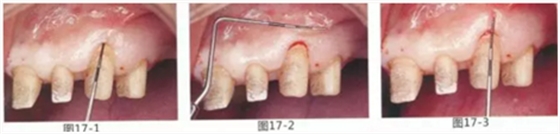

為了在左上1,2,3,4部位增加附著齦,左上1,2部位用Apically Positioned Flap(齦瓣根尖側(cè)轉(zhuǎn)移),左上3,4部位用游離齦移植的病例

圖17-1~3 左上3的牙周袋探測(cè)值為3mm,角化牙齦寬度為2mm。也就是完全不存在附著齦,如果這種狀態(tài)下佩戴修復(fù)體的話,很有可能發(fā)生頸部暴露等問(wèn)題。

圖17-4 左上1,2進(jìn)行齦瓣根尖側(cè)轉(zhuǎn)移,左上3,4進(jìn)行游離牙齦移植,在去除牙周袋的同時(shí)獲取附著齦。

圖17-5 牙周治療完成后的正面照。左上3,4部位處游離齦移植片的上端通過(guò)骨膜縫合固定在頰側(cè)嵴頂部。這樣可以使其愈合效果與齦瓣根尖側(cè)轉(zhuǎn)移相同。